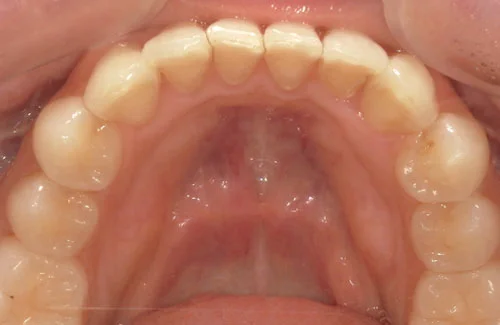

<症例7>歯がガタガタで噛み合わせが悪くお悩み

抜歯無し・マウスピースのみで矯正した症例です。

もともと歯列弓が非常に狭く、V字に近い形をしていたので噛み合わせも非常に不安定でした。

また、下顎前歯部がかなり上の方に生えていたため、下の前歯が上の前歯を突き上げてしまい出っ歯の状態になっていました。

現在では見た目はもちろん、臼歯の噛み合わせも改善しております。

患者様と症状

主訴:歯のガタガタ、噛み合わせが悪い

性別・年齢:20代女性

問題点:叢生(重度)、V字歯列弓、ディープバイト

診断:前歯部の叢生を伴うアングルⅠ級、骨格性Ⅰ級の不正咬合

主なリスク:臼歯の移動に伴い一時的に咬合しにくくなる、歯肉退縮

症状:叢生(そうせい) 過蓋咬合(かがいこうごう)

治療内容

治療期間:1年10ヶ月

治療費用:990,000円(税込)

プラン:Full2プラン

抜歯:無し

再診治療費:無し

追加治療費:無し

保定装置費:無し

治療前後の写真